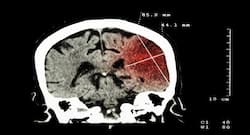

There are different kinds of stroke one can experience an ischemic stroke, haemorrhagic stroke or TIA or transient ischemic attack often termed as a silent stroke. While no one is immune to stroke, there could be certain risk factors that can make one prone to it.